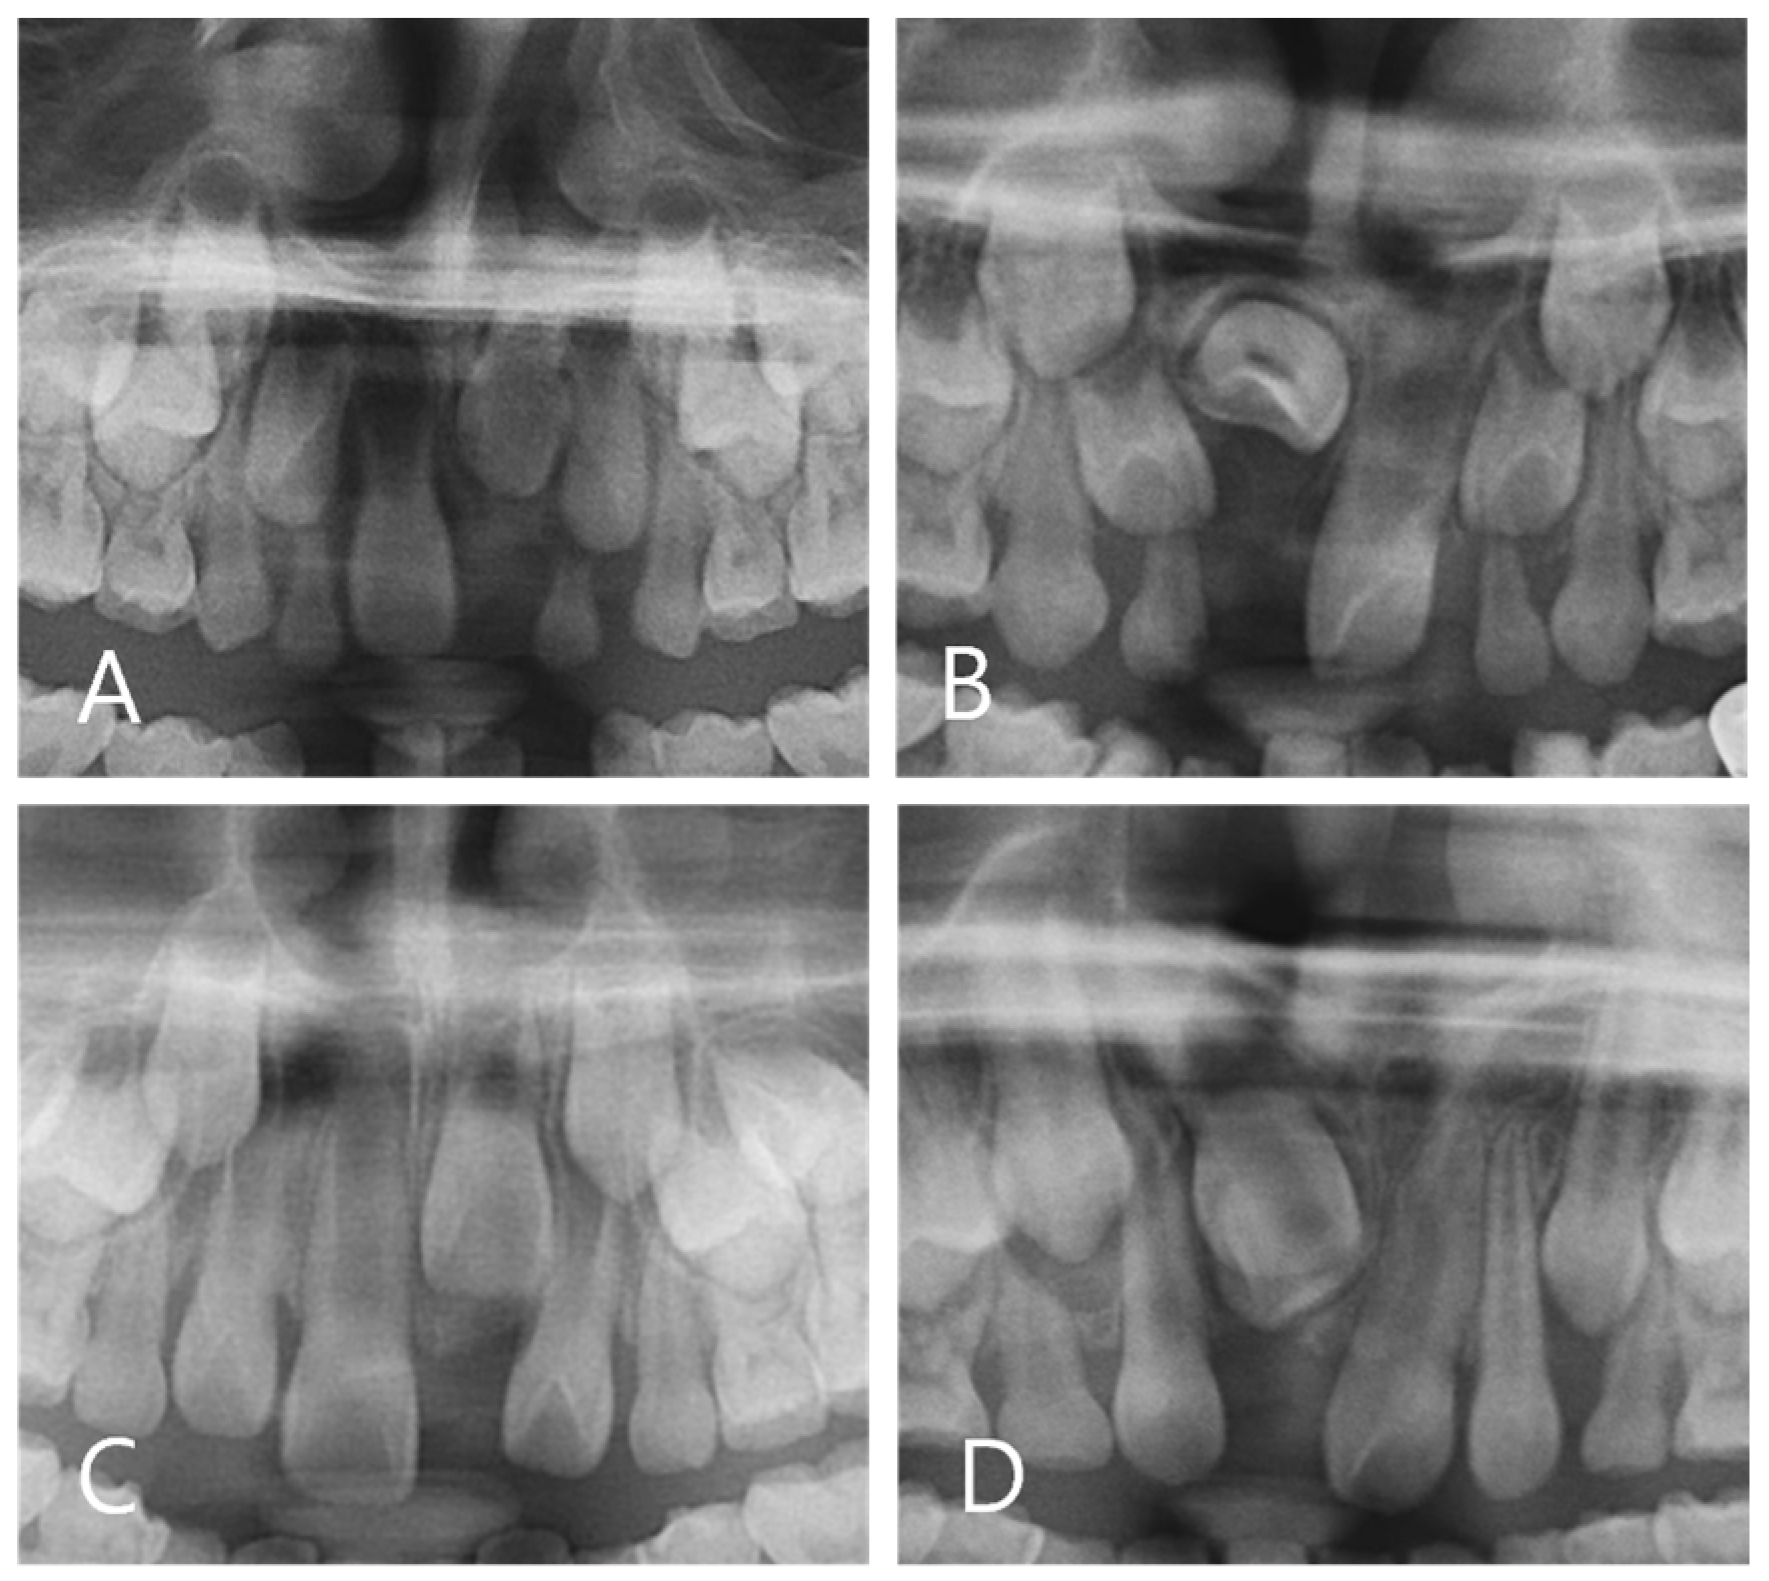

2.3. Panoramic Radiograph